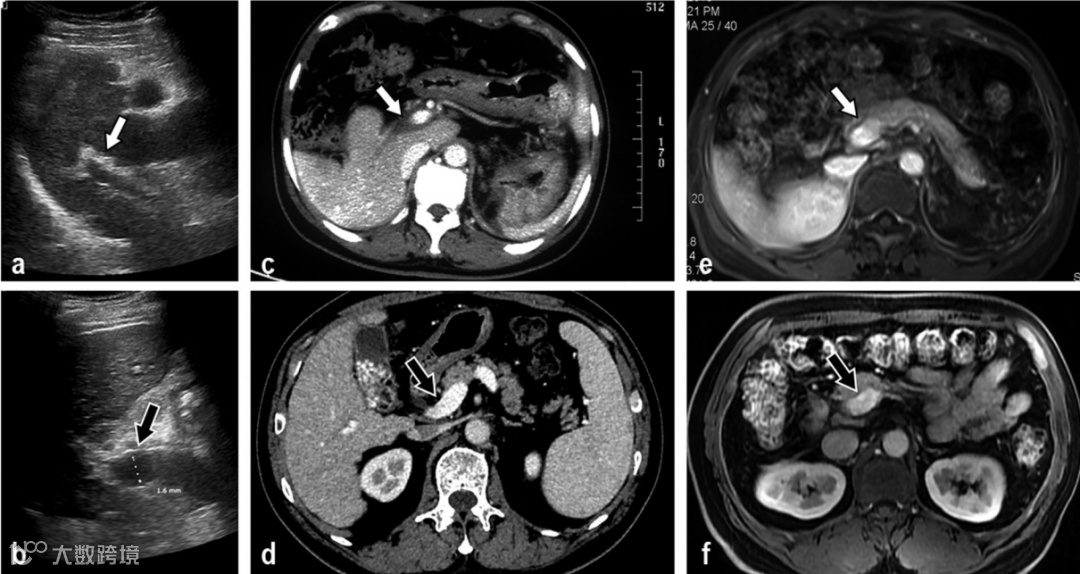

该回顾性研究分析了2015年1月至2019年3月间的共16例IPH和16例肝硬化患者(年龄为39±20岁)的超声、CT和MRI图像和病理结果,以及对照组的16例正常人成像结果。

结果发现,IPH与肝硬化患者的门静脉主干和门静脉矢状部的平均管腔直径、壁厚和厚径比间存在显著差异(P<0.05);在第3段(S3)门静脉、IPH和肝硬化患者之间管腔直径和厚径比之间也存在明显差异(P<0.05)。在IPH患者中,主要影像学改变是门静脉壁增厚、狭窄或闭塞、造影剂延迟期门静脉的较低强化区域以及T1WI的非均匀变化。相应的病理学变化包括小叶间静脉增厚、狭窄、闭塞、门静脉纤维化及肝细胞萎缩或凋亡。肝硬化的主要影像学特征是T1W1表现为结节性改变,相应的病理学改变是假小叶形成。IPH的影像学特征包括门静脉血管壁增厚、管腔狭窄和无弥漫性肝硬化样结节。

因此,两种疾病的影像学特征具有明确的病理学基础,对IPH和肝硬化的鉴别诊断有帮助。

目前,尚无关于有效的影像检查鉴别这两种疾病的报道。本研究回顾性总结了IPH与肝硬化的超声、CT及MRI的影像特征,并与相应的病理进行对照分析。结果显示,IPH的影像学和病理学主要表现为Glisson鞘与门静脉系统的破坏,影像学表现为门静脉管壁增厚并轻度延迟强化,门静脉管腔狭窄、闭塞,门静脉周围肝实质不均质表现;病理学表现为门静脉管壁纤维化,门静脉周围肝细胞萎缩、凋亡,病理与相对应的影像表现相吻合。与IPH不同的是,肝硬化门静脉管壁变薄、管腔扩张,肝实质弥漫性再生结节形成,尤其在T1WI-MRI尤为明显;其病理主要特征为肝实质纤维化,小叶间可见纤维间隔,假小叶形成。故IPH与肝硬化在影像学和病理学上都有明显的区别。因此,IPH区别于肝硬化最主要的影像特点是无弥漫性肝硬化结节、增厚的门静脉管壁以及门静脉管腔狭窄,这些影像特征同时加上明确的病理基础,可有效进行两者的鉴别诊断。